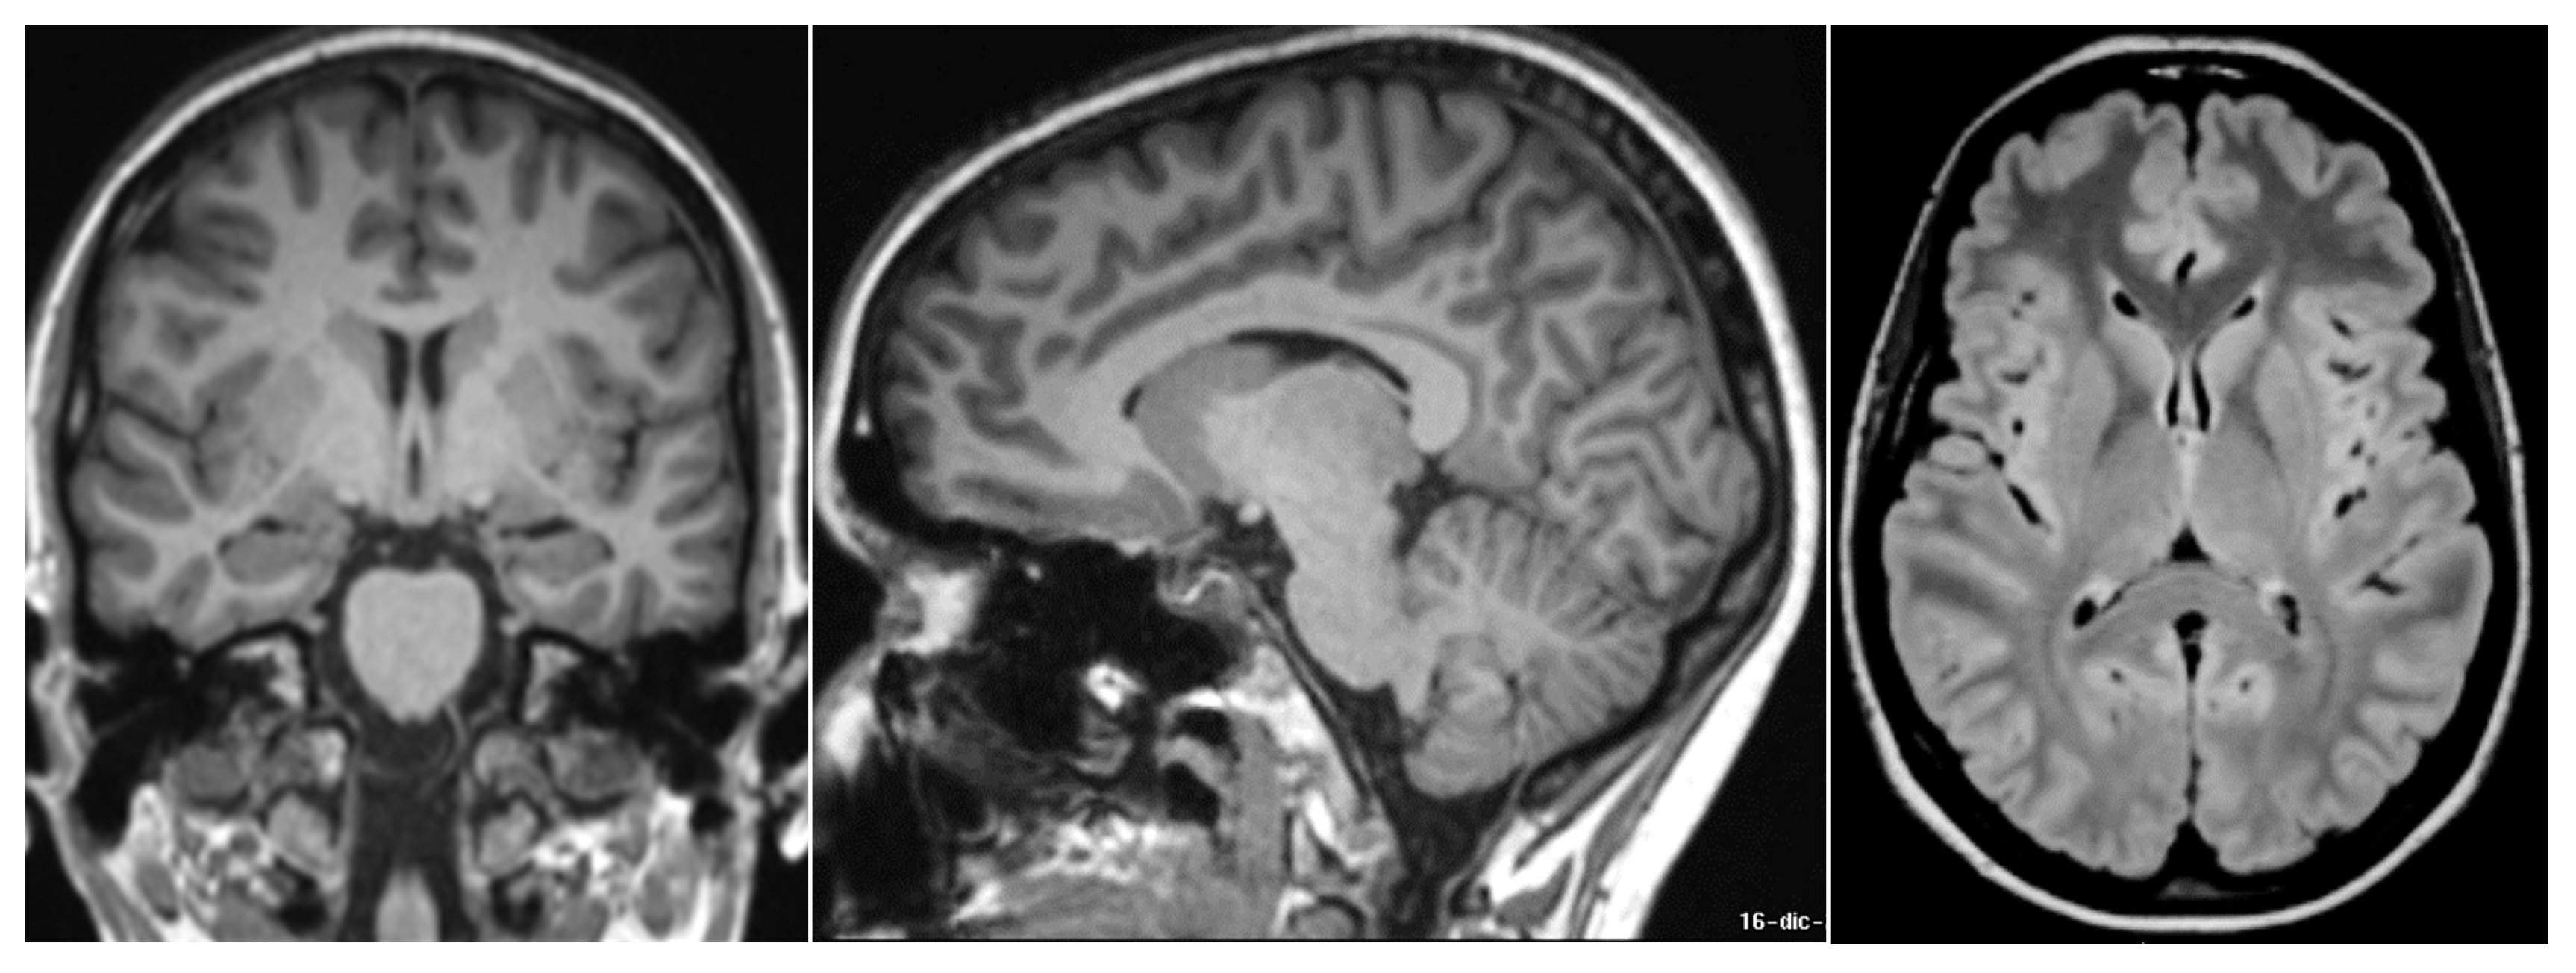

Persistent 18F-FDG Brain PET Fronto-Temporal Hypometabolism and Cognitive Symptoms Two Years after SARS-CoV-2 Infection: A Case Report

2. Case Description